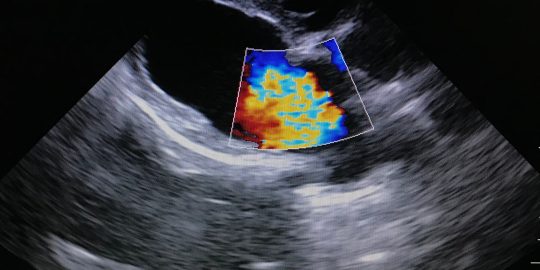

Pulmonic stenosis (also called pulmonary stenosis) is a serious condition of the heart. It is often congenital, meaning your dog is born with it, and the first indication of a problem may be when a heart murmur is picked up during a routine puppy check by your vet. Being tol…